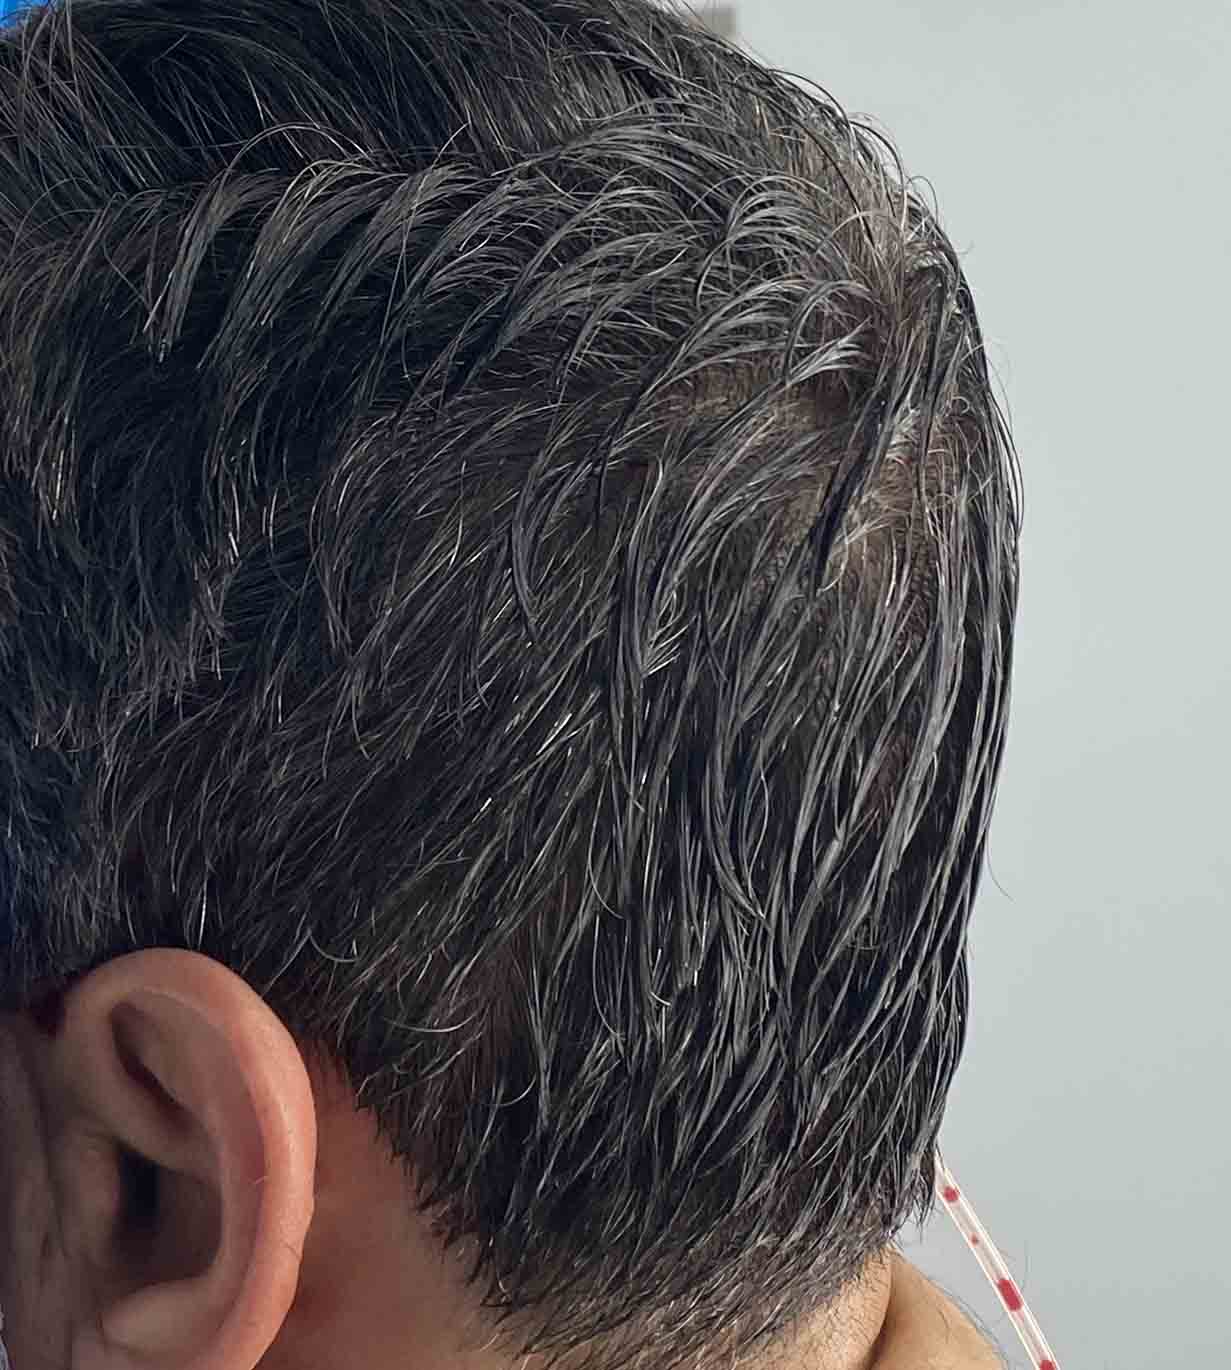

Long haired male with desire to augment a congenital flat back of the head.

Placement of custom back of head skull implant without trimming or shaving any hair. The incision was hard to find postop.

Long haired male with desire to augment a congenital flat back of the head.

Placement of custom back of head skull implant without trimming or shaving any hair. The incision was hard to find postop.